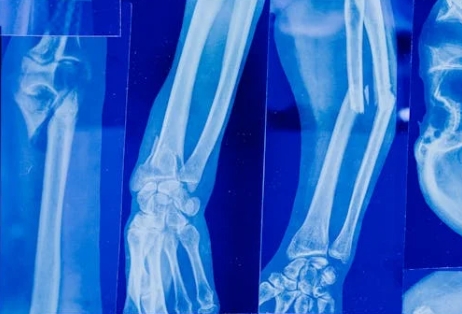

钙流失会导致骨密度降低,骨骼变得脆弱不堪,骨折风险大幅增加。骨质疏松症更是“悄无声息”的找上门,尤其偏爱老年人和绝经后女性。一旦患上骨质疏松,轻微碰撞甚至咳嗽都可能引发骨折,严重影响生活质量,还可能带来长期的疼痛与行动不便。